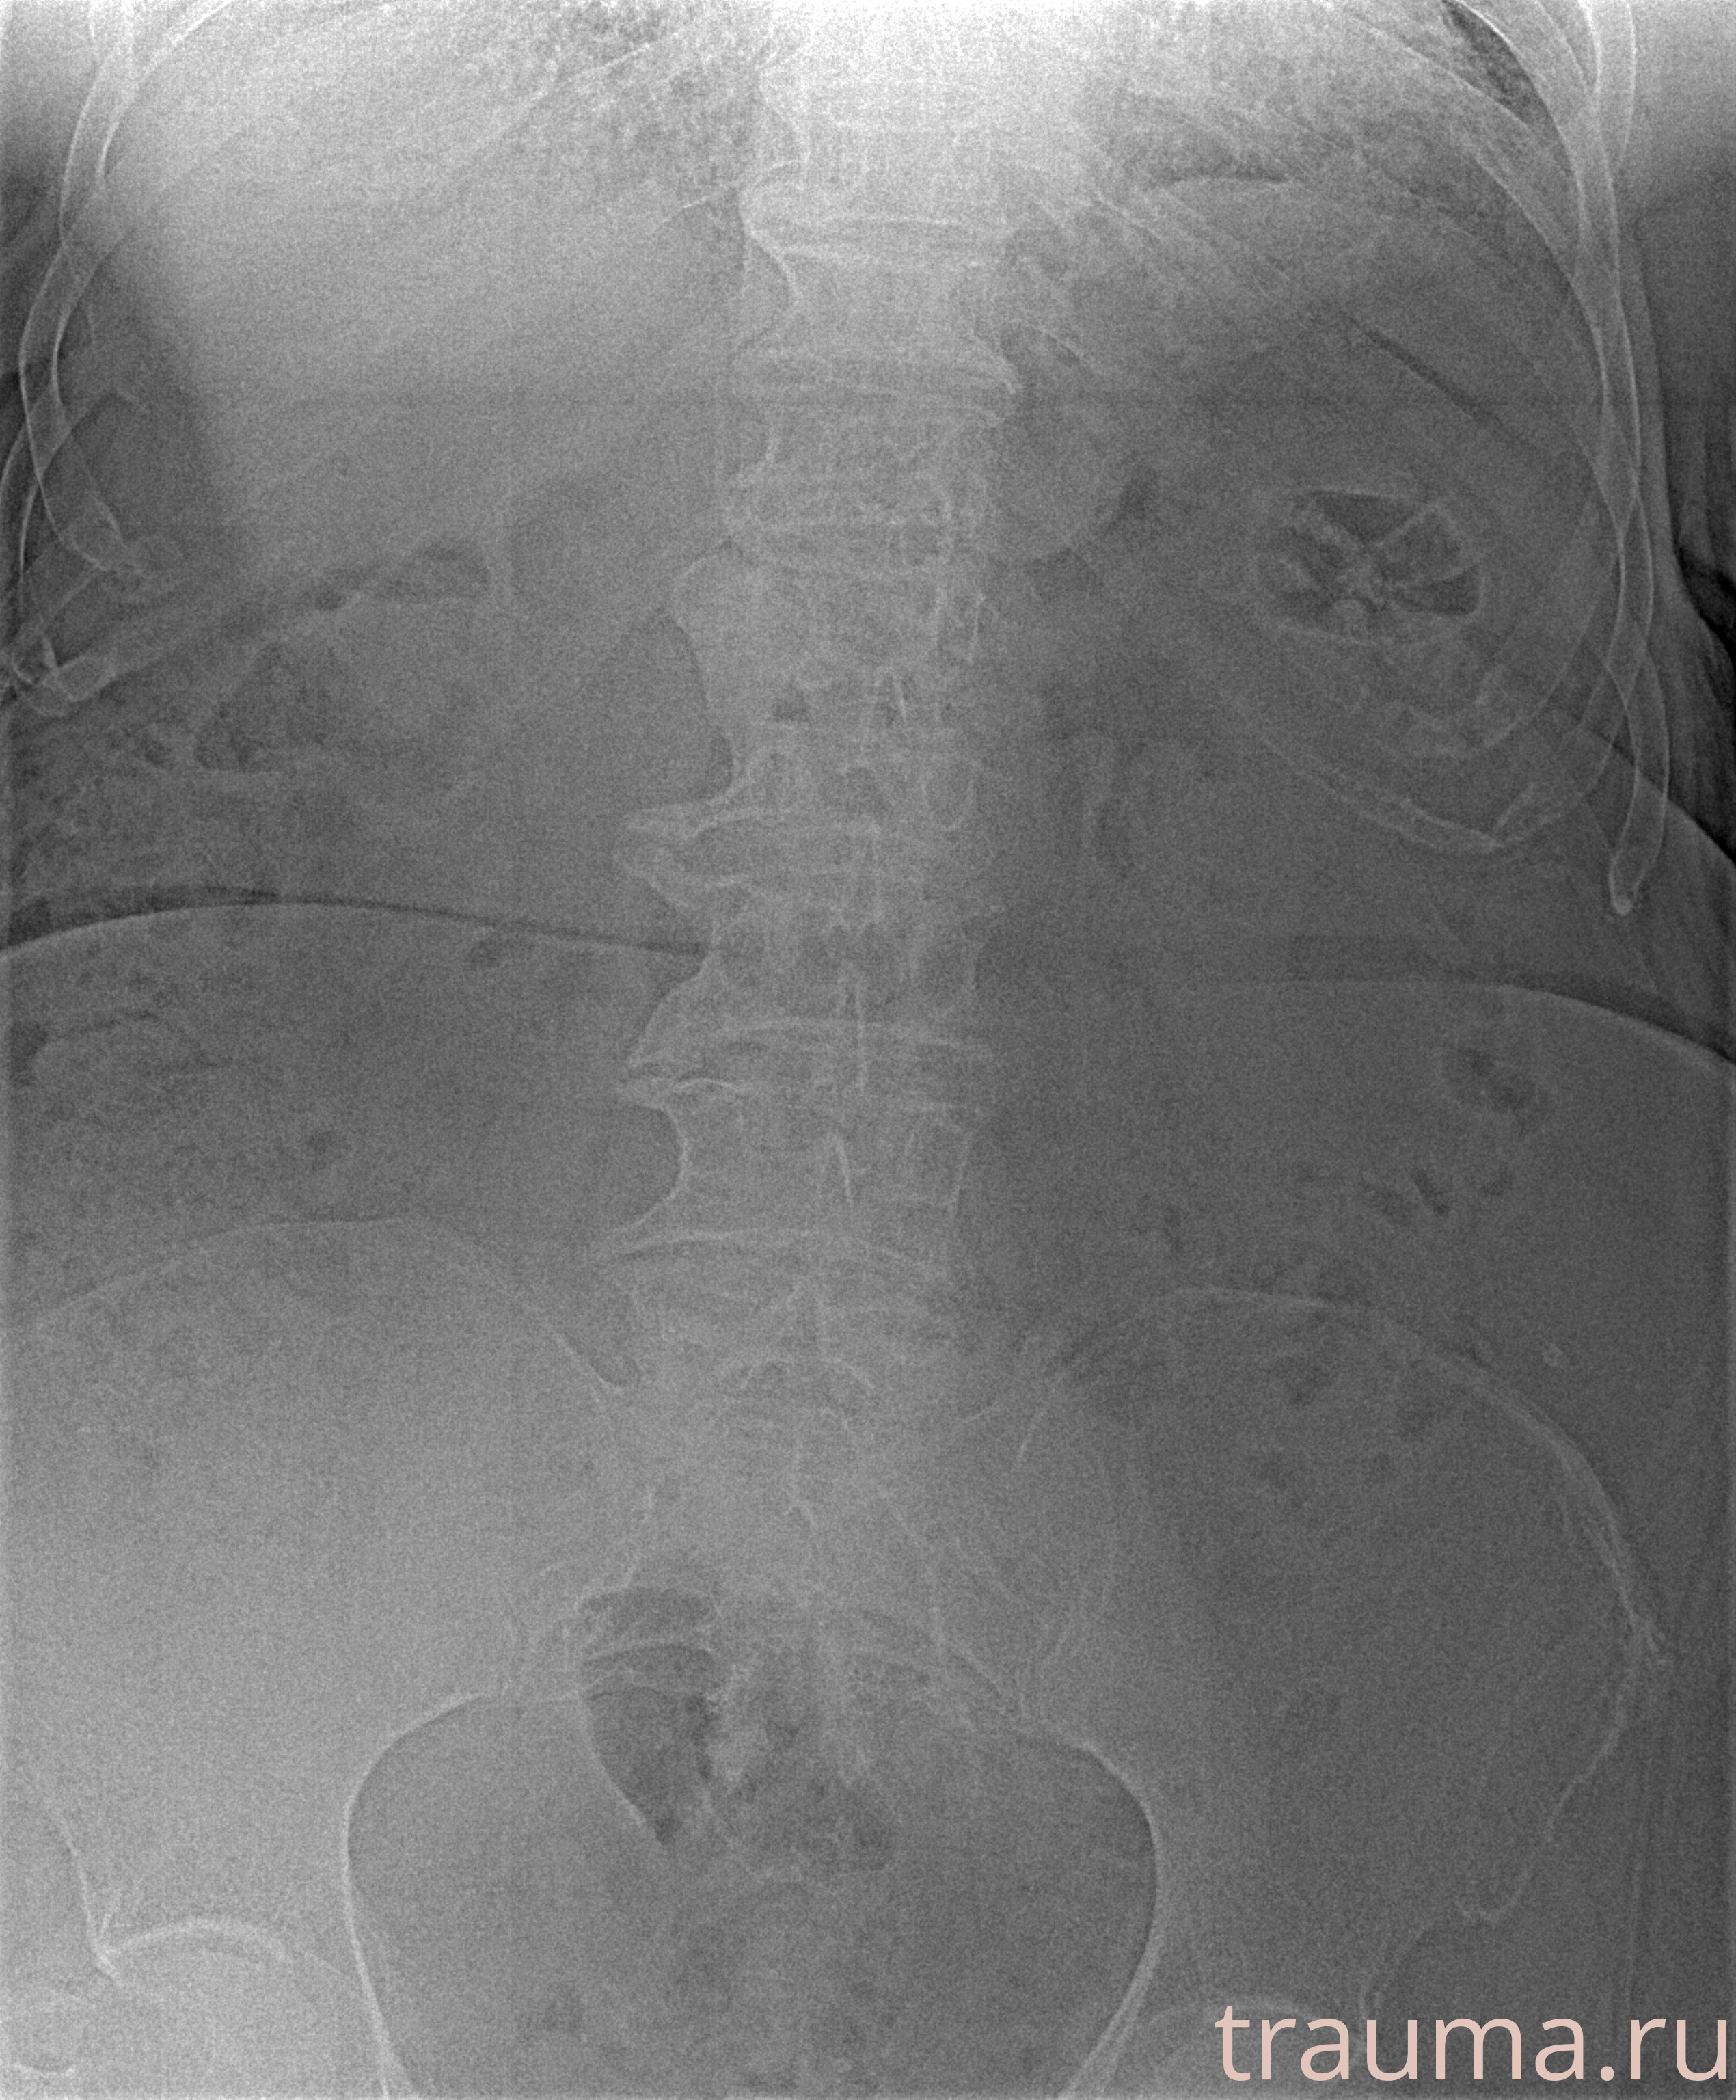

Рентген на дому: по вашему адресу приезжает врач-рентгенолог, травматолог-ортопед с мобильным рентгеновским аппаратом, проводит диагностику травмы или заболевания, делает необходимые рентгенограммы, дает рекомендации по дальнейшему лечению. Получить качественные снимки в домашних условиях возможно благодаря уникальной методике, разработанной МосРентген Центром для института  Склифосовского

при переломе шейки бедра и пневмонии от компании МосРентген Центр - партнера Института имени Склифосовского